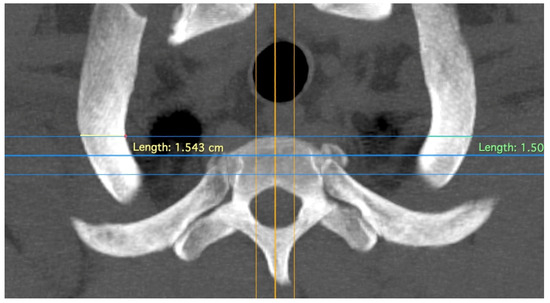

| Variable Name | Abbreviation | Description |

|---|---|---|

| Rib width | R | Minimal width of the rib at the height of the front edge of the first thoracic vertebral body. |

| Vertebral body width | VBW | Width of the first vertebral body at the level of the centre of the articulatio capitis costae 1 |

| Vertebral body depth | VBD | From anterior edge to posterior edge (most ventral point of vertebral foramen) of the first vertebral body |